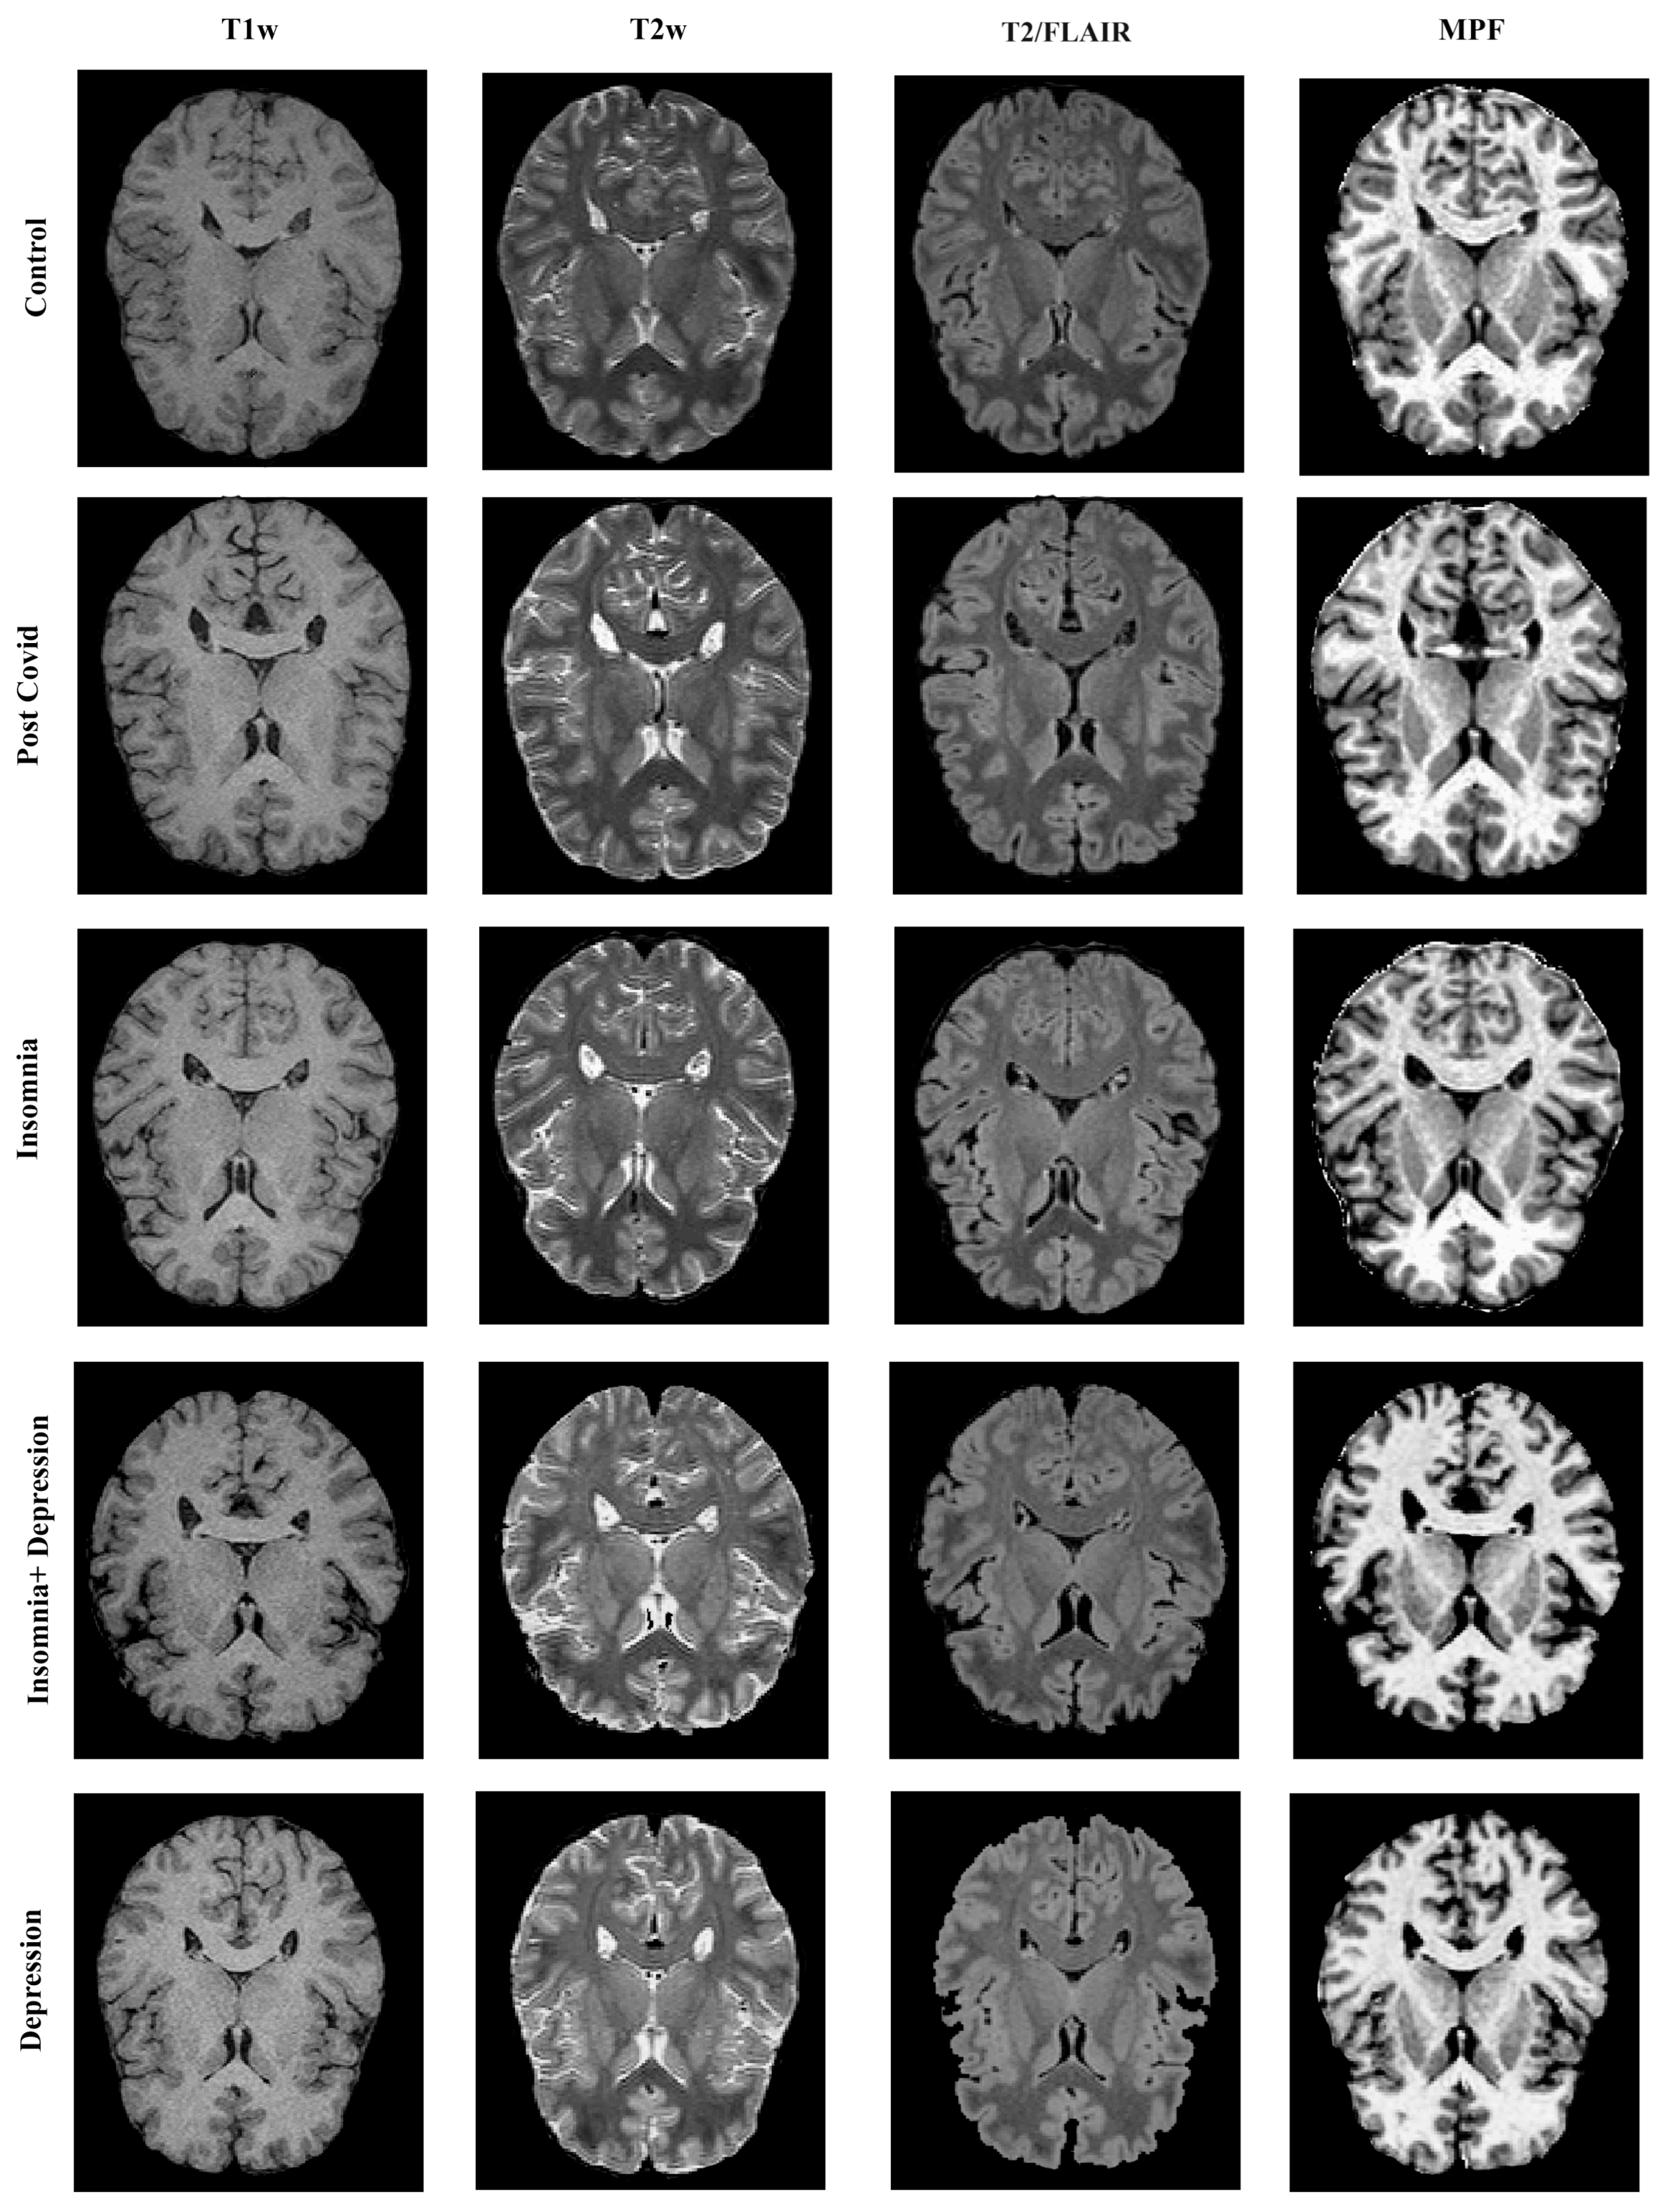

4.3. MRI Data Acquisition

- Magnetization Transfer (MT)-Weighted: TR = 20 ms; echo time (TE) = 4.76 ms; flip angle (FA) = 8°; scan time: 5 min 40 s;

- T1-Weighted: TR = 16 ms; TE = 4.76 ms; FA = 18°; scan time: 4 min 32 s;

- Proton Density (PD)-Weighted: TR = 16 ms; TE = 4.76 ms; FA = 3°; scan time: 4 min 32 s.

- 3D Fluid Attenuated Inversion Recovery (T2/FLAIR): TR = 5000 ms; TE = 390 ms; TI = 1800 ms;

- 3D T1-Weighted: TR = 16 ms; TE = 4.76 ms;

- 3D T2-Weighted: TR = 3000 ms; TE = 335 ms.

4.4. Image Processing